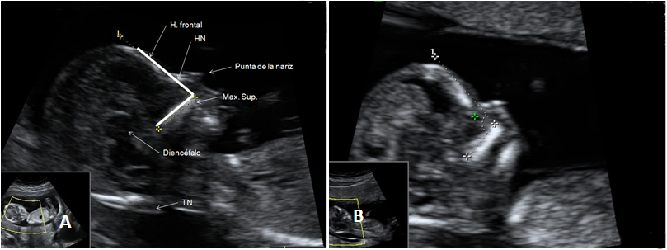

Diagnóstico de siameses de 11 semanas de gestación

Ecografía Embarazo 2D y 3D Semana 12 - PRUEBAS DIAGNÓSTICAS